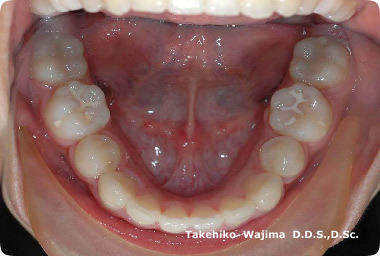

| 口腔内所見 | 犬歯、大臼歯関係はアングルU級で、上下顎とも著しい叢生が認められた。 |

| 批評・予後 | 上顎第一小臼歯抜歯により上顎は叢生の改善、下顎第二小臼歯抜歯により下顎大臼歯部の近心移動によりアングルT級の緊密な咬合が獲得され、バランスのとれた口元に改善された。 |